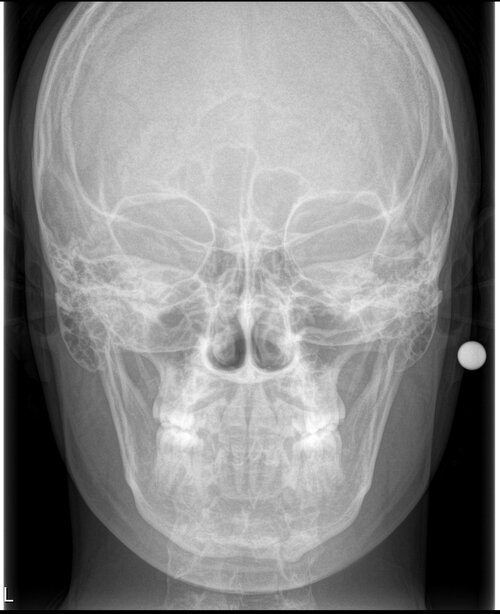

Current bite shown in the RX i know for sure my upper teeth need to go back by a lot to allow good movements thanks to being a camouflaged class 3

Current bite shown in the RX i know for sure my upper teeth need to go back by a lot to allow good movements thanks to being a camouflaged class 3